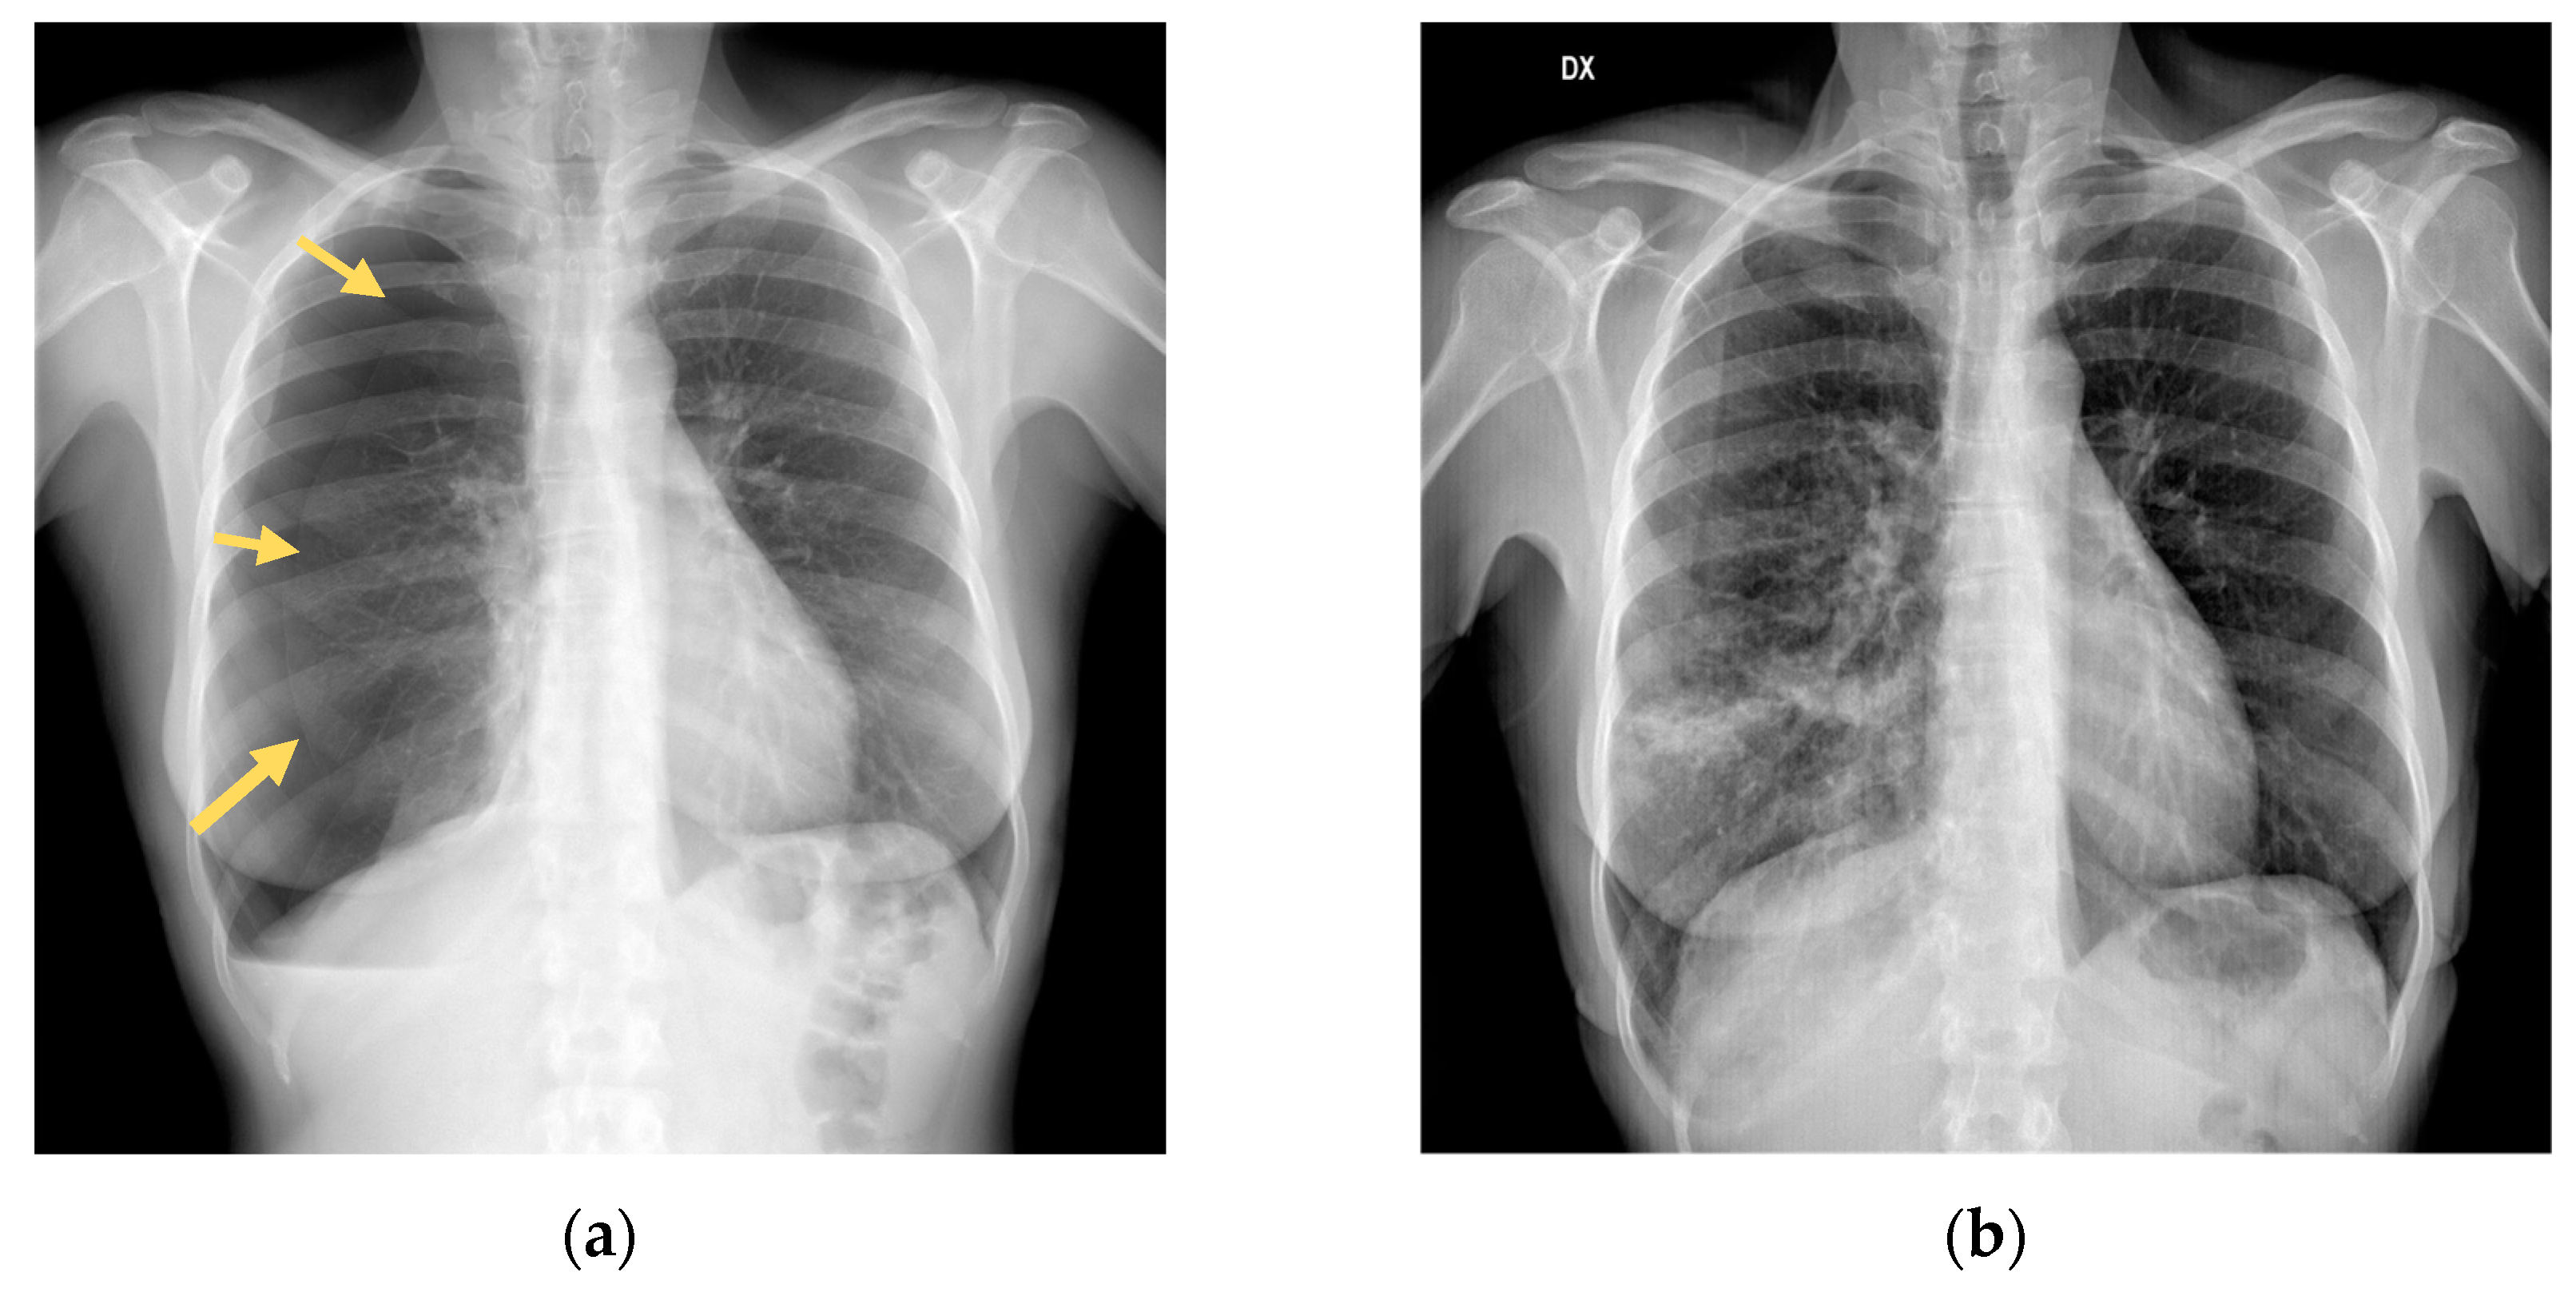

Following a car accident, a 52-year-old Italian woman with no significant past medical or surgical history presented to the local French Emergency Department (ED). Diagnostic workup with chest x-ray and CT revealed one non-displaced rib fracture in her right fifth rib, as well as a right-sided pneumothorax, and fracture of the transverse processes of T11-T12-L1-L2. The patient refused admission despite medical advice to accept hospitalization and returned to Italy, where she immediately presented to our Emergency Department. She complained of pain in her right chest and tenderness on palpation of the dorsal spine (Visual Analog Scale score 6). A repeated chest x-ray revealed a right-sided pneumothorax measuring 55 mm. (Figure 1a). The patient’s blood pressure was 135/86, her heart rate was 71/minute; she was eupneic with a respiratory rate of 18/min with an oxygen saturation of 96%. We decided to perform needle aspiration after multidisciplinary discussions with our trauma surgeons. A 14 Fr cannula was inserted under local anaesthesia in the second intercostal space near the midclavicular line in a sterile field. A total of 1500 ml of air was aspirated. The patient was admitted to our medical unit for close observation. Serial chest x-rays performed on day-1 and 2 demonstrated a significant reduction in pneumothorax size. (Figure 1b). The patient was discharged after 4 days with a chest x-ray showing a 5 mm right pneumothorax. Follow-up at 10 days by chest x-ray showed complete resolution of the pneumothorax flap.

Figure 1. a) Initial chest X-ray shows a right pneumothorax of 55 mm; (b) Chest X ray evaluation, after needle aspiration, shows expansion of lung parenchyma with reduction of pneumothorax.